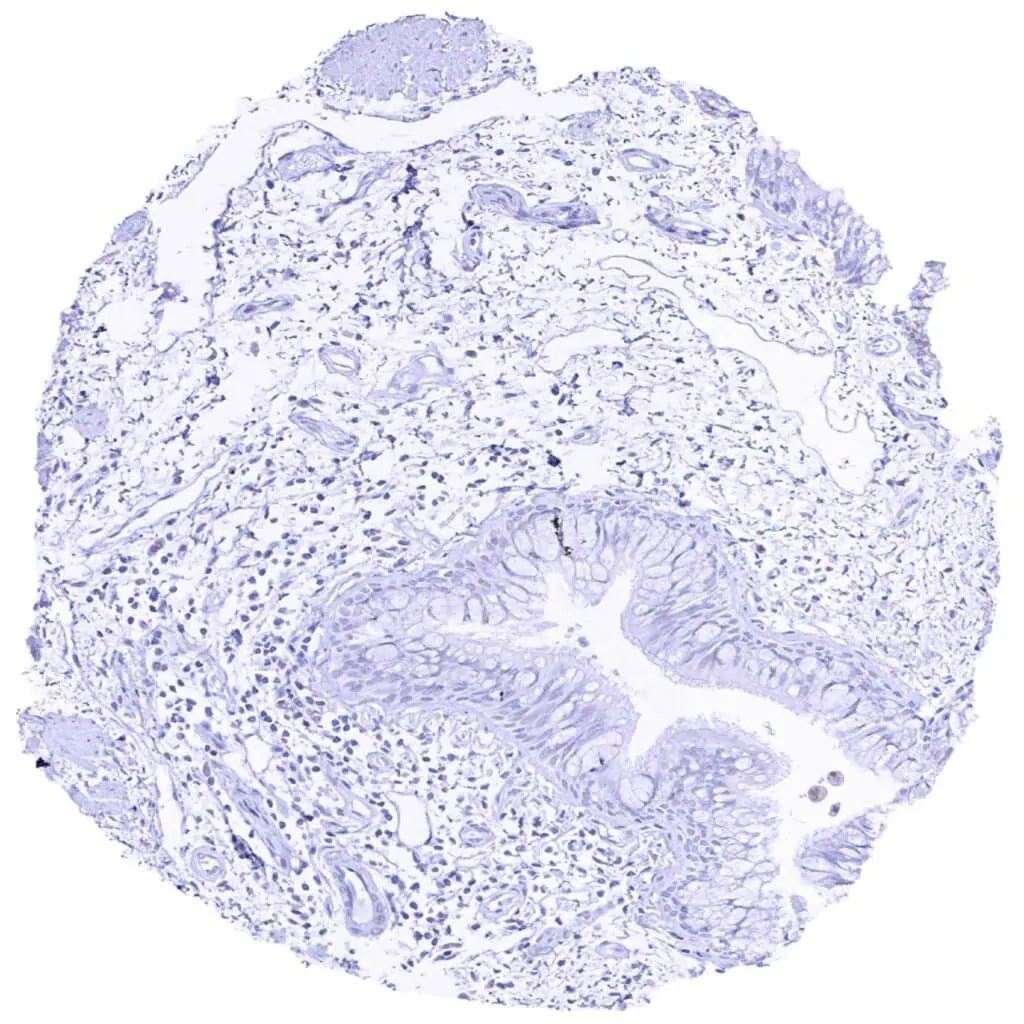

Sinus paranasales – Weak to moderate Cyclin E1 staining of a subset of inflammatory cells